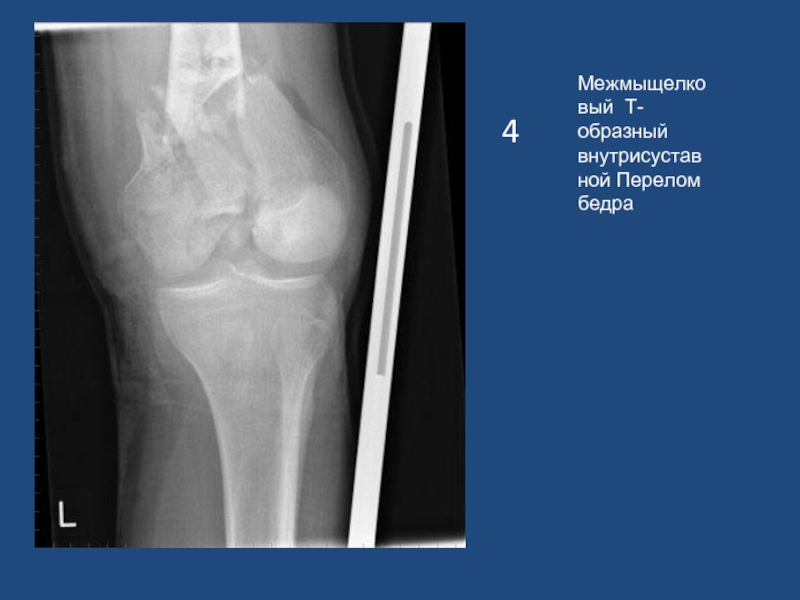

Слайд 54

Межмыщелковый Т-образный внутрисуставной Перелом бедра